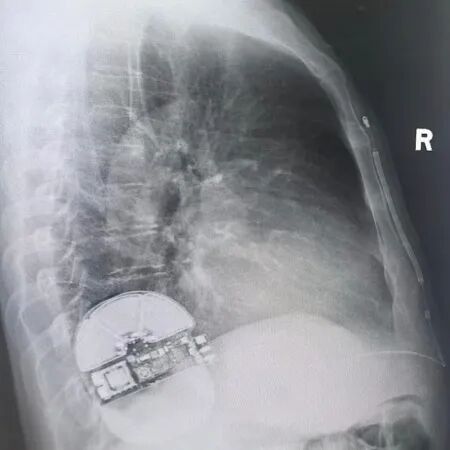

(术后影像)

由于患者EF值低,经讨论后未进行诱颤,经计算PRAETORIAN 评分<90分,无(低)DFT风险,故放弃诱颤。整个手术过程顺利,术后患者生命体征平稳,耗时不到1小时,患者无明显疼痛感觉。术后程控:电学参数正常,系统阻抗70欧姆,除颤线圈紧贴胸骨,除颤器机壳紧贴肋骨,影像完美。患者回病房后,优化各项参数,恢复良好,获得了现场专家团队的高度认可。